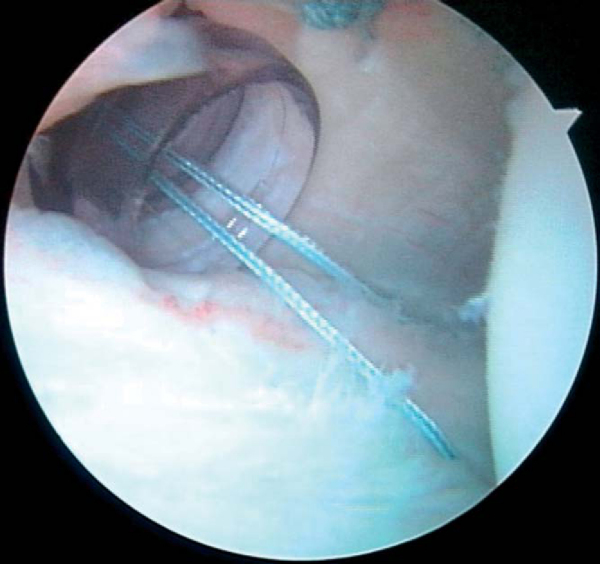

| • | After placement of the suture anchors, a 45-degree Spectrum suture hook (Linvatec, Largo, Fla) is loaded with a No. 0 polydioxanone (PDS) suture (Ethicon, Inc., Somerville, NJ). The contralateral side hook is chosen (i.e., a left 45-degree hook for a right shoulder when it is introduced from the posterior portal). Alternatively, there are other commercially available suture passers and suture relays that will also suffice. | |

| • | The suture passer is delivered through the torn labrum and advanced superiorly, reentering the joint at the edge of the glenoid articular cartilage ( Fig. 8-11 ). |

|

| • | In the setting of a labral tear with some capsular laxity, the suture passer is advanced through the posterior capsule approximately 1 cm lateral to the edge of the labral tear and then underneath the labral tear, to the edge of the articular cartilage, the so-called pleat stitch ( Fig. 8-12 ). |

| • | The PDS suture is then fed into the glenohumeral joint, and the suture passer is withdrawn through the posterior clear cannula. | |

| • | An arthroscopic suture grasper is used to withdraw both the most posterior suture in the suture anchor and the end of the PDS suture that has been advanced through the torn labrum. This move detangles the sutures in the cannula. | |

| • | The PDS suture is then fashioned into a single loop and tightly tied over the end of the braided suture. | |

| • | The most lateral PDS suture, which has not been tied to the braided suture, is then pulled through the clear cannula ( Fig. 8-13 ). |